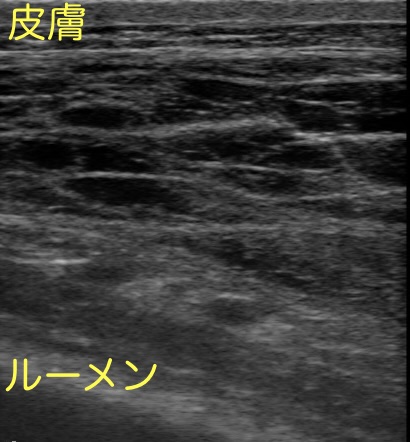

繁殖検診で用いる直腸用プローブを、左下腹部の皮膚に押し当てて見てみました。

二箇所、場所をずらして撮ったものです。

いずれも皮膚と腹腔臓器の間の筋層が網目状に広がっているように見えます。

低エコー(黒っぽく映ること)に映るのは炎症により血管から漏出した漿液または血液と推察されます。

消化管(内腔に流動性が見られる管腔状の構造)は映らず、均一な構造でもないことから、類症鑑別①②の可能性は否定されました。